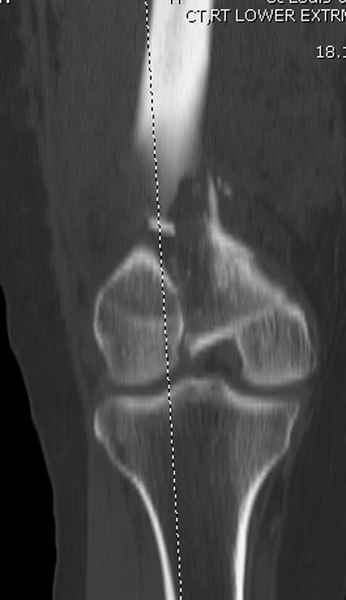

Имя     : distal femur crm 2.jpg

Тип     : image/jpeg

Размер  : 13023 байтов

Описание: отсутствует

Url     : http://weborto.net:8080/pipermail/ortho/attachments/20081001/5646c87e/attachment-0013.jpg